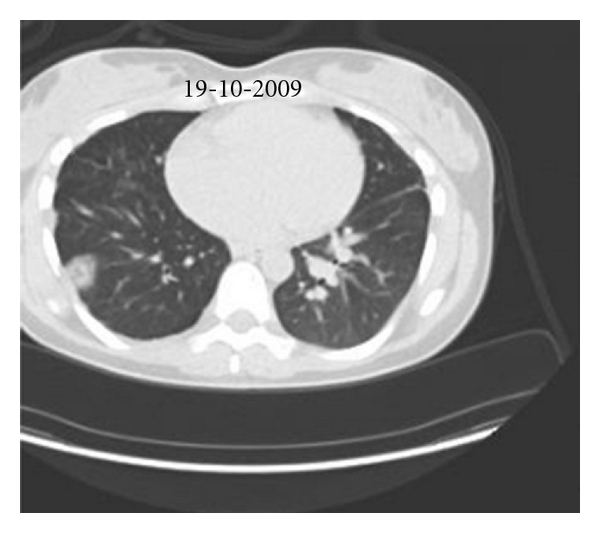

Routine laboratory examination did not show any signs of inflammation. Electrocardiogram was normal. Echocardiogram showed a thickened mitral valve, a tricuspid regurgitation of 3/4 with an estimated systolic pulmonary arterial pressure (PAP) of 60 mmHg, and a markedly dilated, mildly hypocontractile right ventricle. Right heart catherisation showed a mean PAP of 28 mmHg, a cardiac index of 2.91 L/min/m2, and a total pulmonary vascular resistance of 450 dyne.sec.cm−5. Exercise capacity was impaired as shown by a 6 min walking distance of 553 meters (69% of predicted) with desaturation from 96 to 90% and by an ergospirometry showing a peak oxygen consumption of 22 ml/min/kg with desaturation from 97 to 83%. Lung function was normal except for a low diffusion capacity of 46%. Chest X-ray showed enlarged pulmonary arteries with a right parahilar nodule, perfusion scan multiple lobar and segmental defects, and pulmonary angiography amputations of the right lower lobe and left upper lobe arteries, with multiple aneurysmal dilatations of the branches of the right upper lobe artery (Figure 1). CT of the chest confirmed the presence of a nodule in the right upper lobe, which was metabolically active on PET scan (Figure 2(a)).

In our patient, a 4-item differential diagnosis was discussed: (1) CTEPH, but angiography was somewhat atypical and pulmonary hypertension was mild; (2) Takayasu arteritis [1], but without systemic inflammation or proximal systemic artery disease at CT, MRI, and PET scans; (3) mycotic pulmonary aneurysms [2], again without systemic inflammation or chronic infection; (4) pulmonary artery intima sarcoma, but without proliferative process in central pulmonary arteries. After local as well as international multidisciplinary consultations, we initially rejected the diagnosis of pulmonary intima sarcoma and tackled the diagnosis of Takayasu disease by treating the patient with high doses of oral corticosteroids combined with ongoing anticoagulation. After 2 months of therapy, evolution was characterized by clinical deterioration with appearance of cough, brown and sometimes bloody expectorations and intermittent fever, by a slightly increased CRP (19 mg/L, <5), and by progression of the lesions on Chest X-ray (Figure 3), CT (Figure 4), and PET (Figure 2(b)) scans. The right upper lobe nodular lesion was enlarged, while a thin-walled large cavity had replaced a previously known pleural based condensation in the right lower lobe. A bronchoalveolar lavage showed aspergillus fumigates colonization and voriconazole was added to the therapy while corticosteroids were downtitrated. Retrospectively, we found evidence for infiltrates followed by infarction/cavitation also in the upper segment of the left lower lobe. As intima sarcoma of the pulmonary artery with distal embolisation was the most probable diagnosis, it was decided to perform a pulmonary endarterectomy later completed by lung resection and/or chemotherapy with tyrosine kinase inhibitors according to cell type. While the macroscopic aspect of the surgical material was suggestive for CTEPH, histopathology confirmed the diagnosis of undifferentiated intima sarcoma. In our patient the disease progressed unfortunately very rapidly after surgery with ICU readmission on day 9 because of chest pain, severe progressive hypoxemia, and hemoptysis. As CT scan showed multiple infiltrates and recurrent obstruction of the right lower lobe artery it was decided to withhold therapy. Autopsy showed (i) residual intima sarcoma in the peripheral branches of both pulmonary arteries, with complete or partial vessel wall invasion and extravascular extension (Figure 5), (ii) a myxoid nodular mass, 3 cm in diameter, in the right middle lobe, (iii) a large “cavity” with myxoid center, more specifically formed by oedematous tumoral tissue forming a lattice-like network responsible for radiolucency, in the right lower lobe. There were no signs of infection or aspergillar invasion.